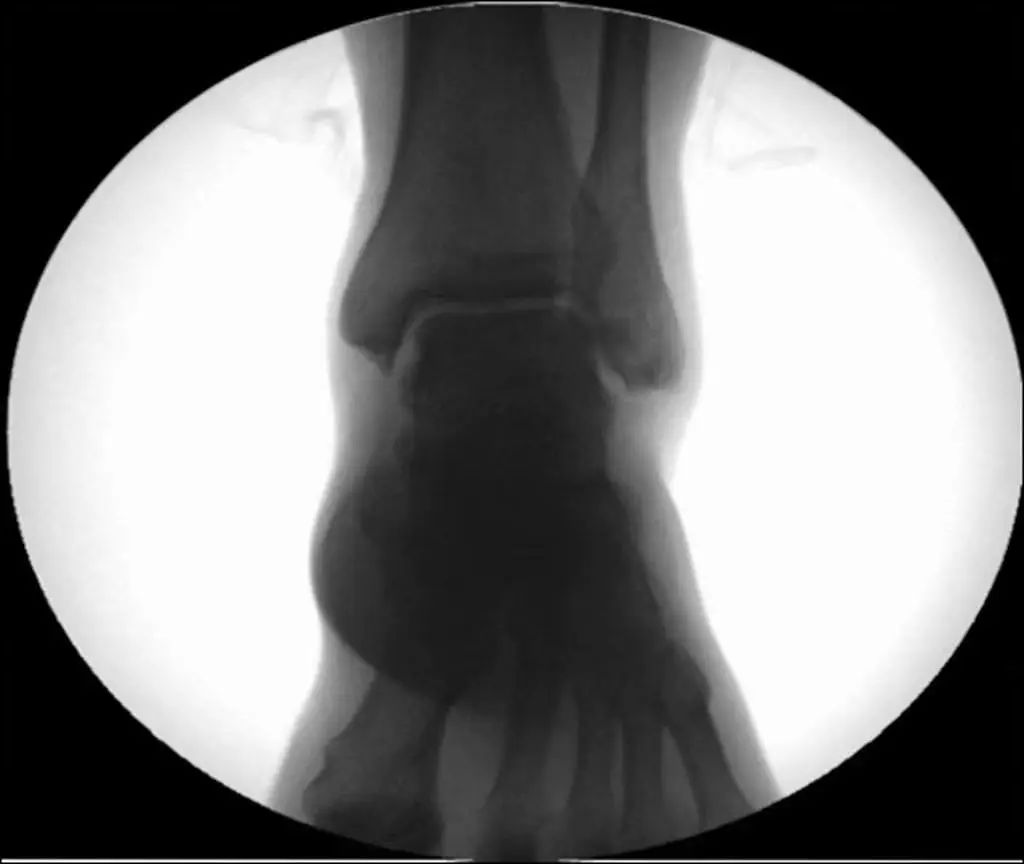

Diagnostic radiographique : L'évaluation standard de l'imagerie de la cheville doit comprendre 3 phases : antéropostérieure (Figure 8), point de cheville (15 ° de rotation interne) (Figure 9) et latérale (Figure 10).

Figure 8 Position avant et arrière

Figure 9 Points de cheville (15° de rotation interne)

Figure 10 Position latérale